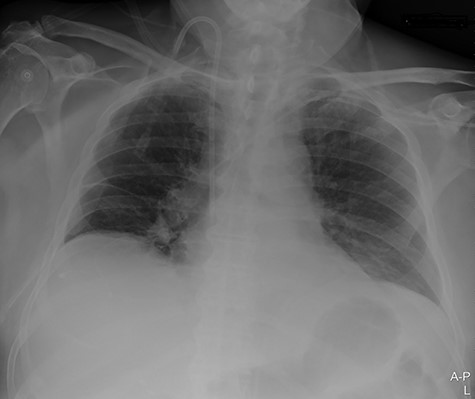

Our surgical team was contacted after 4 h, as the pleural fluid had become grossly haemorrhagic. A CXR showed haemothorax (Fig. 2). Upon clinical deterioration, the patient was intubated, and a 24Ch chest tube was introduced. Approximately, 500 ml of blood was immediately drained, followed by 300 ml during the first 30 min. ICA laceration was suspected. Despite transfusion of red blood cells and plasma and infusion of noradrenaline, the patient remained circulatory unstable. A new CXR showed massive haemothorax despite drainage (Fig. 3). The patient was now utterly haemodynamically unstable and not suited for transportation. As there are no thoracic surgeons or interventional radiologists in our hospital, the general surgeons decided to take him to the operating theatre. A wide anterolateral right thoracotomy was performed with patient lying in left lateral decubitus position. The right pleural cavity was full of fresh and coagulated blood. The pulsating bleeding was seen coming from the posterolateral, caudal chest wall, but the exact site deep down in the sharp costophrenic angle could not be localized and was inaccessible for any surgical haemostatic manoeuvre.

Portable chest X-ray in half-upright position showing massive haemothorax despite chest tube.